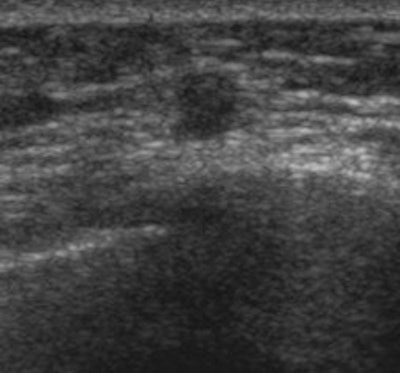

The common ultrasound features were irregular shape, uncircumscribed margins, and hypoechoic masses with intratumoral vascularities. The most common location was within the deep muscle layer, Lee and colleagues wrote.

"When a nodule was oval-shaped, circumscribed marginated, isoechoic, or mildly hypoechoic without any intratumoral vascularity, it was classified as a probably benign finding, corresponding to BI-RADS category 3," they wrote. "We considered rounded nodules or focal nodules with not-circumscribed margins or with any intratumoral vascularity on color power Doppler US as BI-RADS category 4."